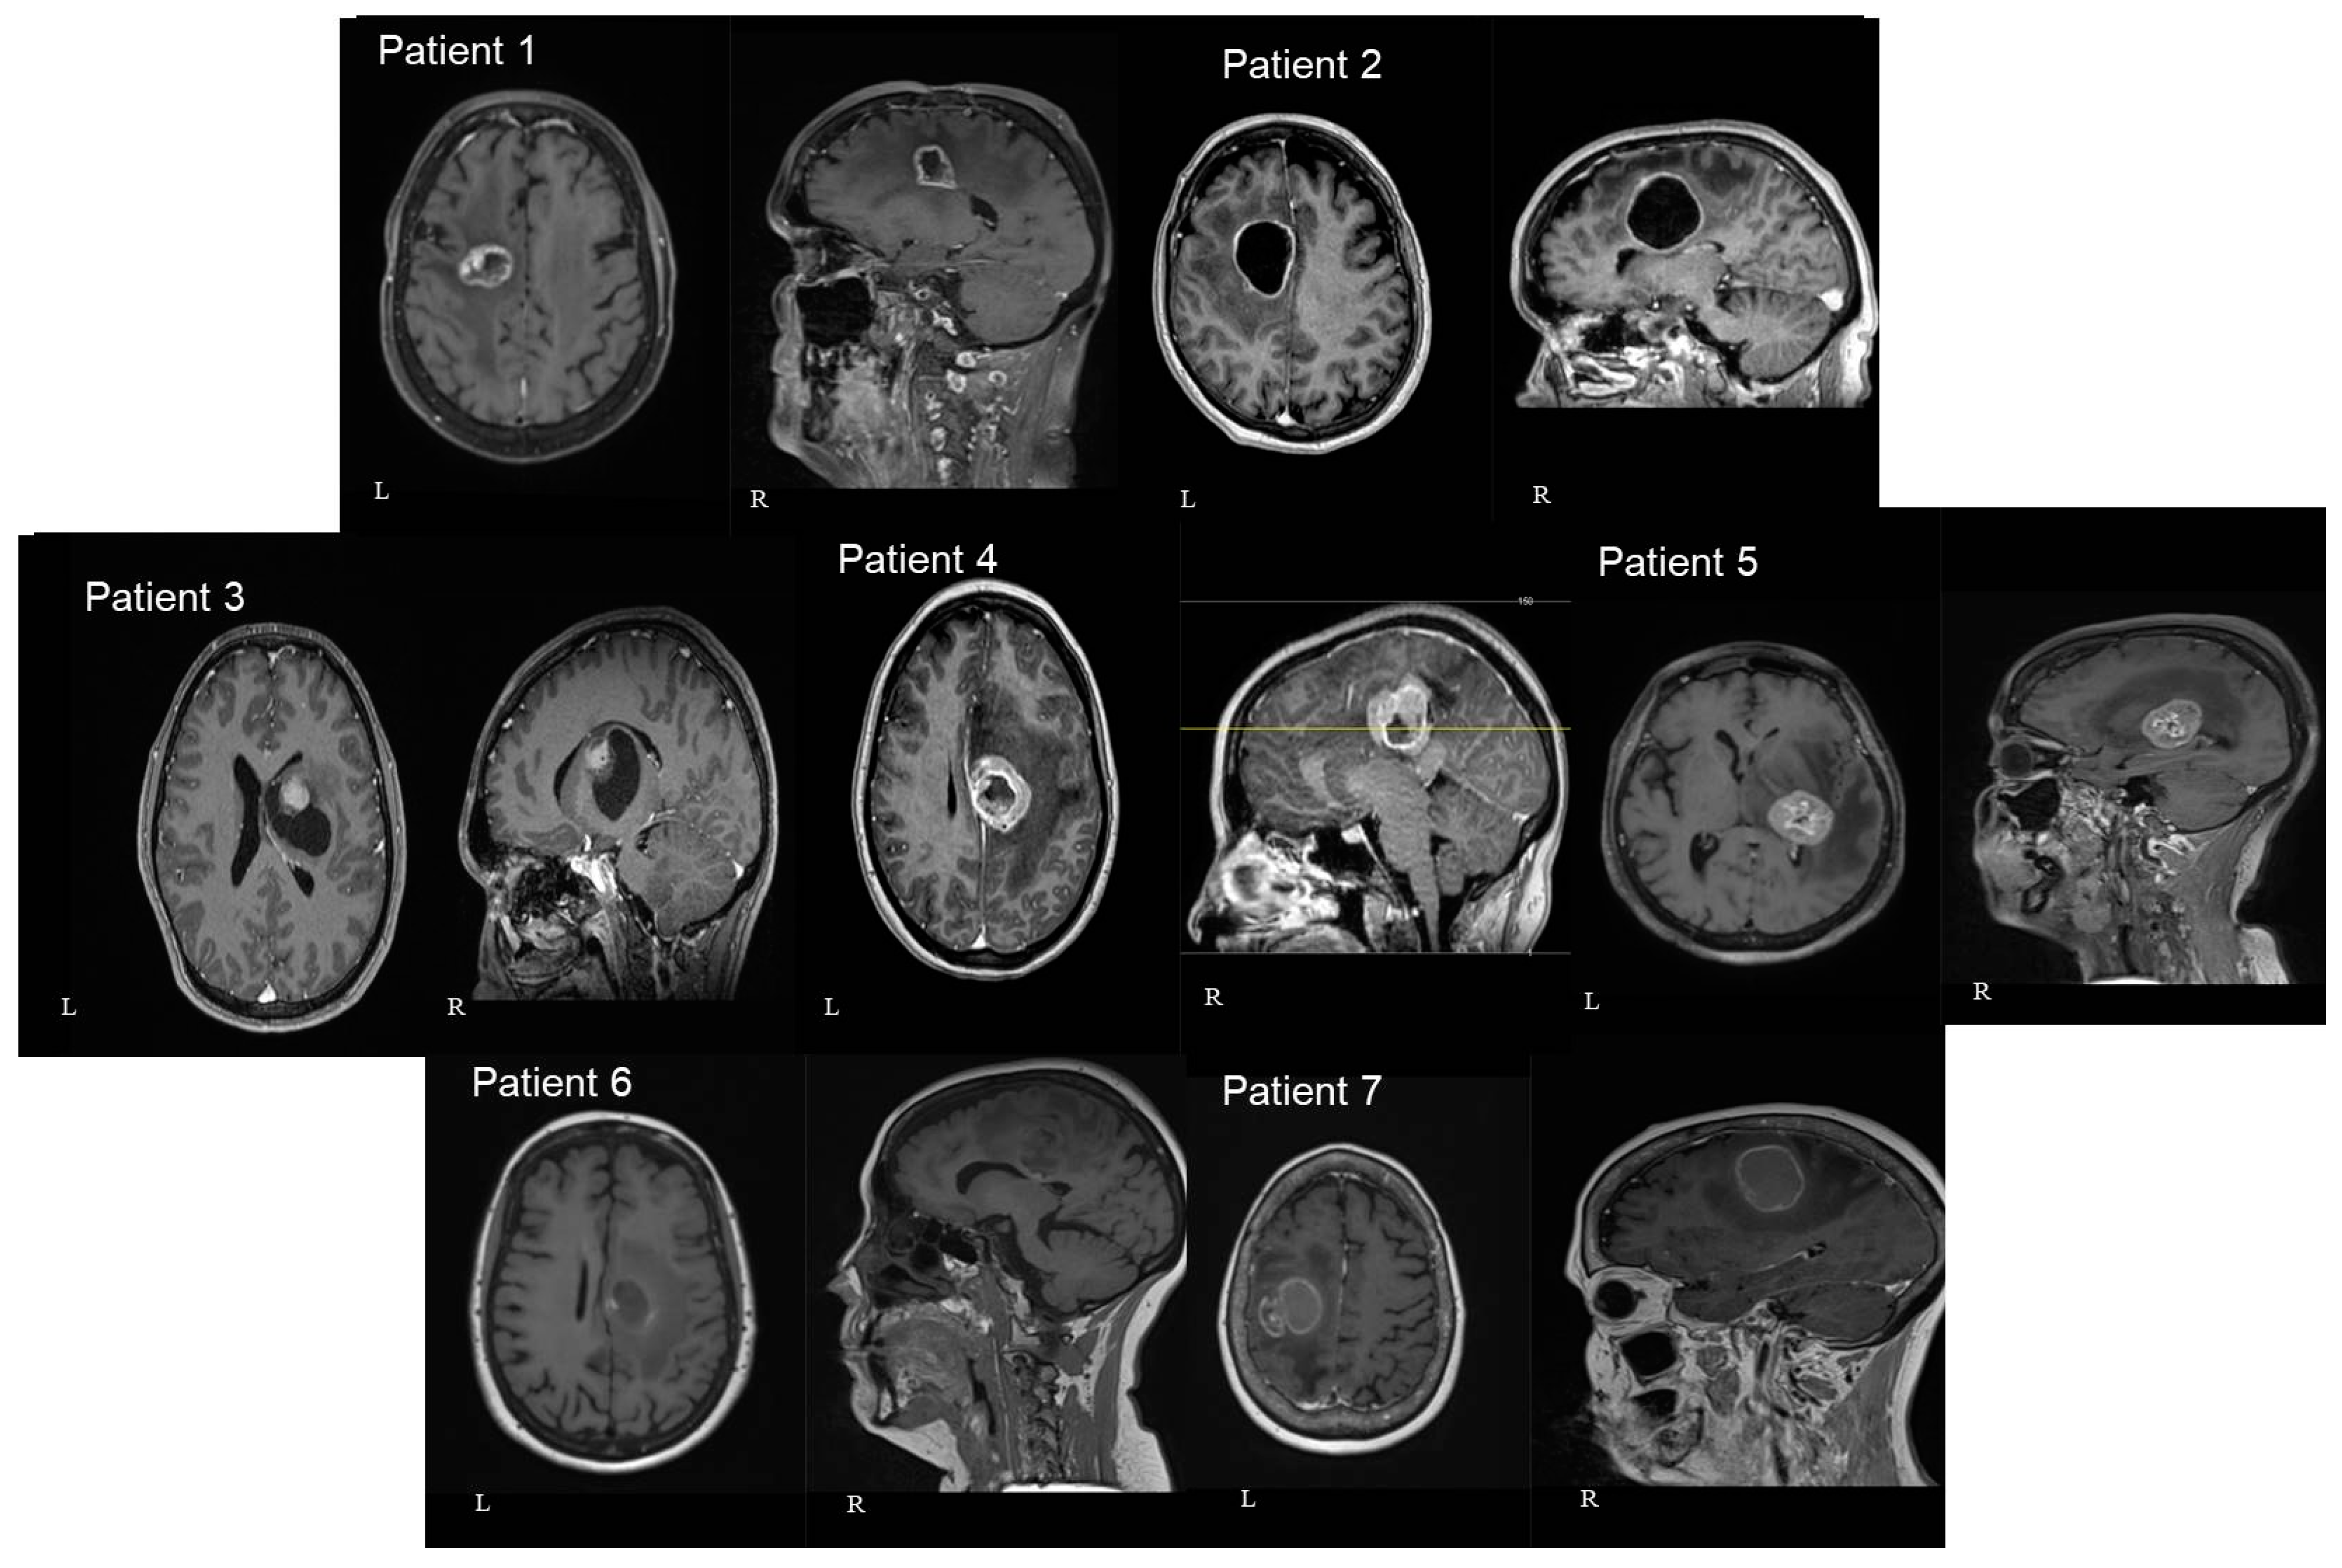

Gross total resection (GTR) was achieved in three patients, and near-total resection (NTR) in four patients (Figure 5). No ischemia was shown in the postoperative imaging and the range of cavity-to-CST distance was 0–4 mm.

Figure 5. Axial pre (left—L) and postoperative (right—R) T1 gad MRI brain images of all seven patients included in our study. A single axial view was selected in order to avoid confusion with multiple images. The number of patients in each image corresponds to the patients mentioned in Table 1 (patient number 7 had only postoperative CTH and no MRI available).